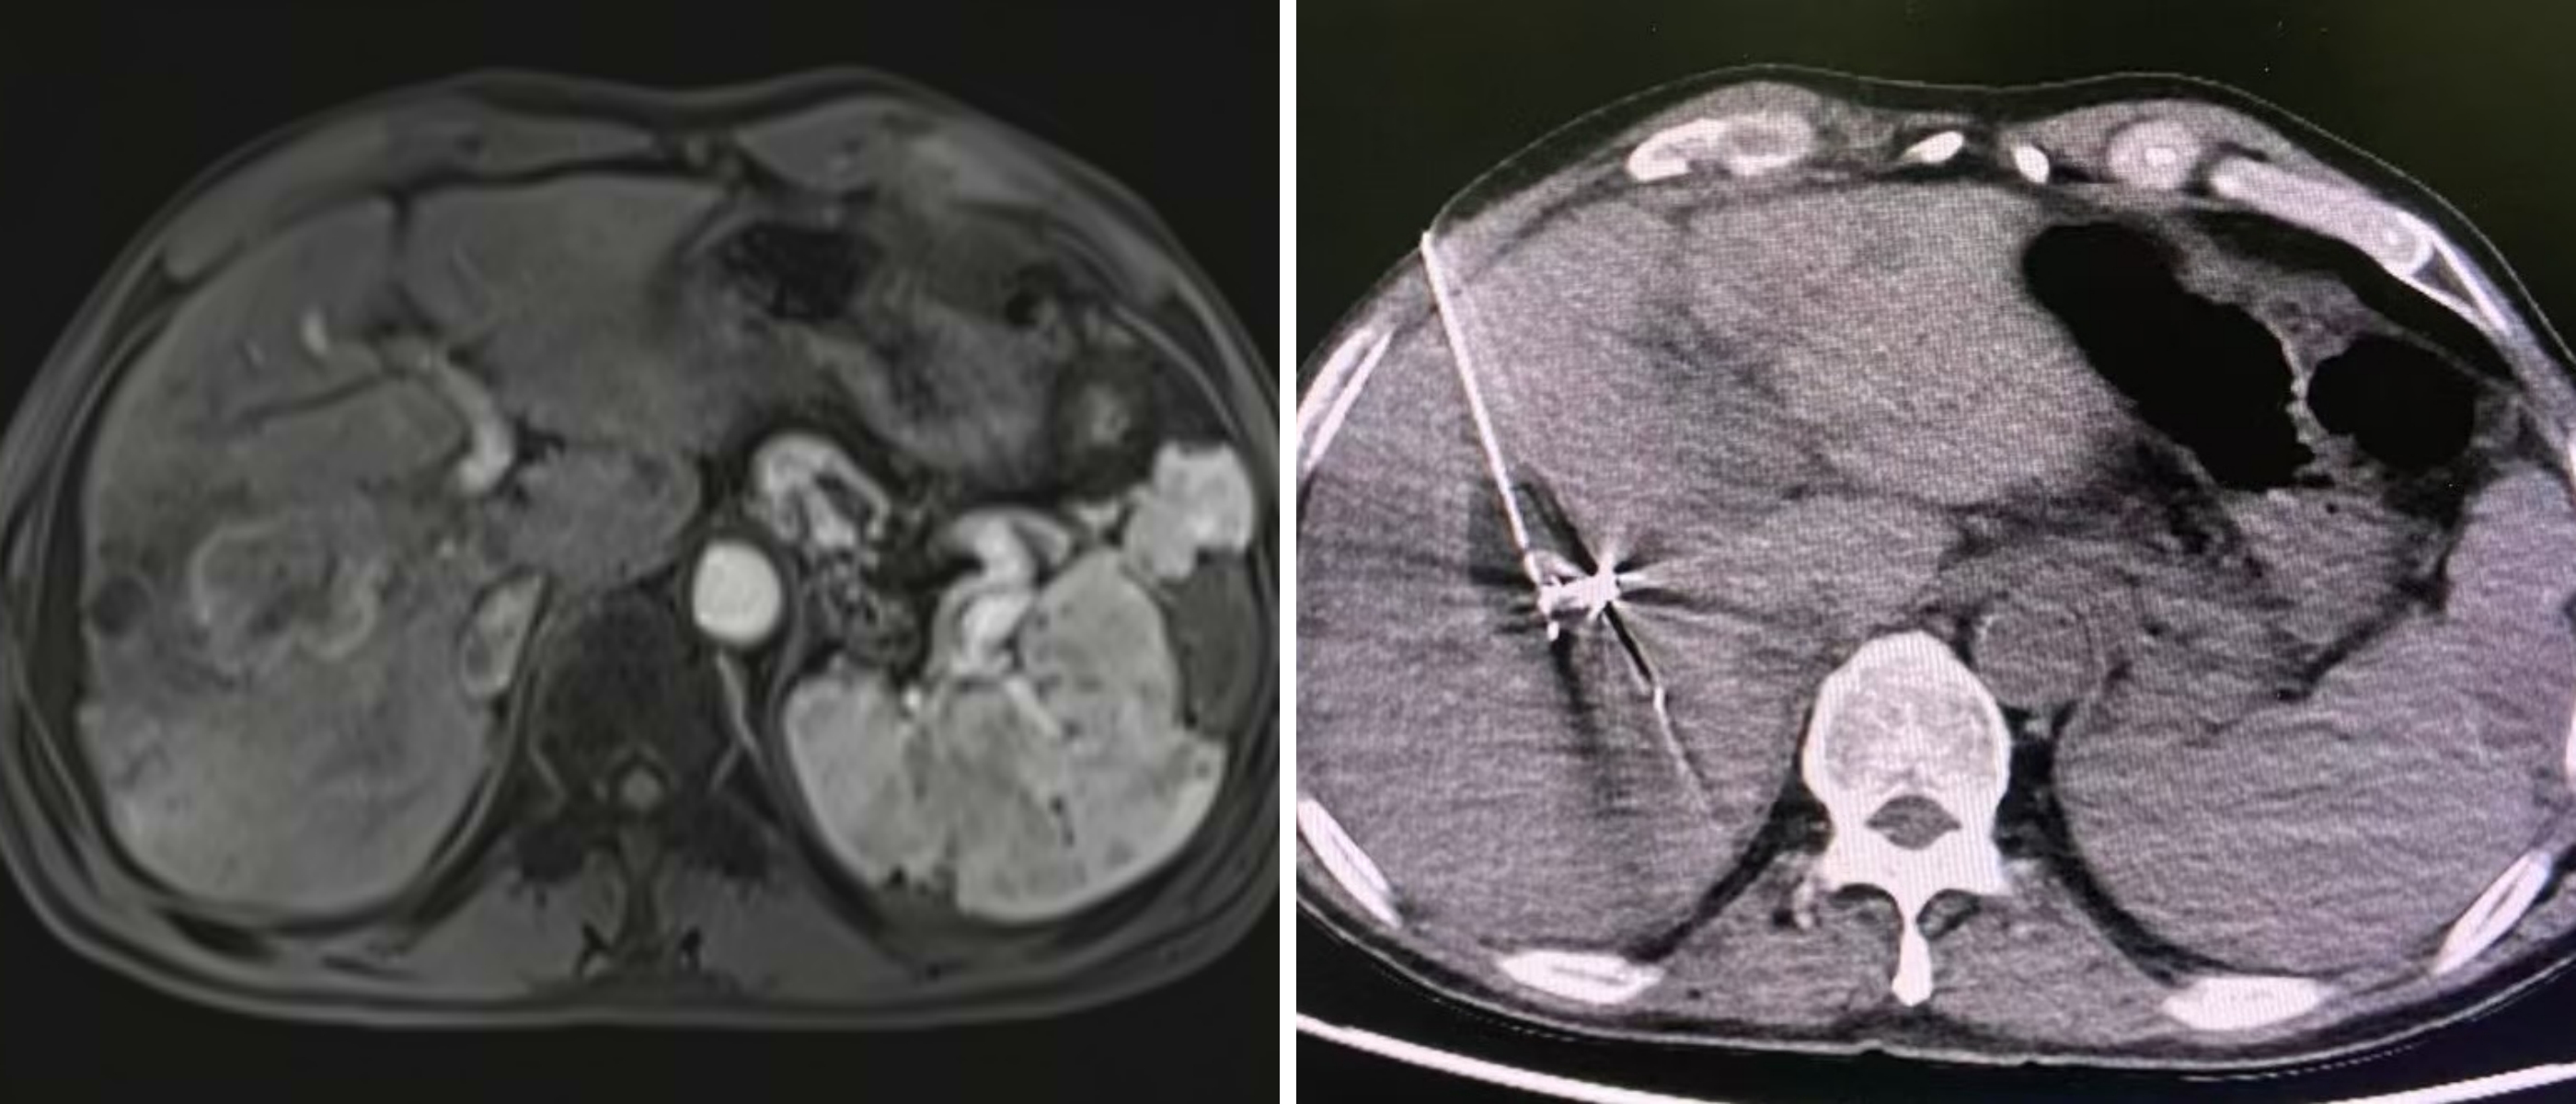

氩氦刀冷冻消融术是一种超微创的肿瘤物理治疗技术。治疗中,医生在影像实时引导下,将仅毫米粗细的探针经皮穿刺至肿瘤中心,通过氩气在针尖急速膨胀制冷,使病灶在数十秒内降至-140℃以下,形成可调控的“冰球”彻底摧毁肿瘤。随后切换氩气快速复温,完成“冻-融”循环。该技术具有创伤小、定位准、恢复快等优势,尤其适用于早期肝癌的根治及部分中晚期患者的减瘤治疗。